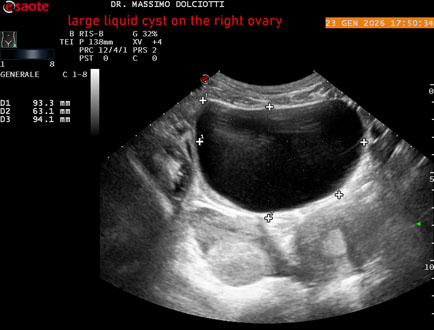

Età Paziente: F 29 anni

Motivazione dell'esame: dolore al lato destro della pelvi in portarice di cisti liquida all'ovaio destro.

Commento all'esame: le immagini ed il video documentano, in sede pelvica, grande formazione anecogena, delle dimensioni di 110 x 60 mm, priva di vascolarizzazione, da ricondurre a grande cisti liquida dell'ovaio destro.

Conclusioni: grande cisti liquida all'ovaio destro (large fluid cyst on the right ovary).